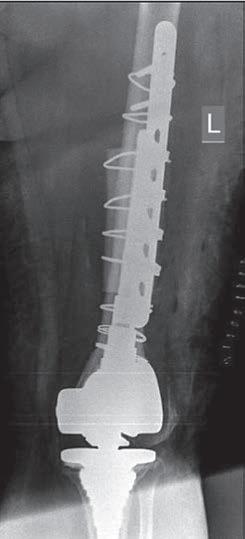

b

Rycina 14.2. Osteokondukcyjne pobudzenie zrostu kostnego belką i przeszczepami kości allogenicznej złamania okołoprotezowego kości udowej lewej po realoplastyce rewizyjnej stawu kolanowego; a) rentgenogram w projekcji przednio-tylnej (a-p), b) rentgenogram w projekcji bocznej (l).